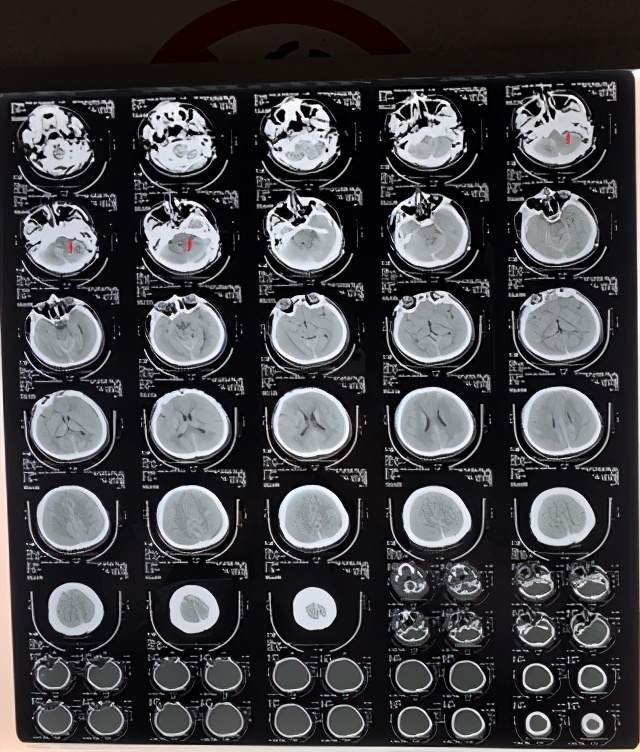

4、根据上述检查,选择枕下乙状窦后入路肿瘤切除术。

5、术后复查CT可见肿瘤切除干净,患者自述听力恢复正常,没有耳鸣、舌麻、头晕、走路不稳等症状,没有面瘫、面部感觉异常等并发症。